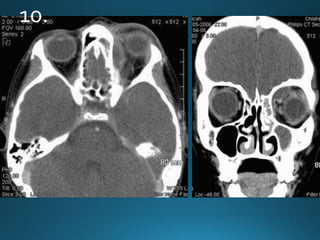

External auditory canal atresia (EACA) is characterised by complete or incomplete

bony atresia of the external auditory canal (EAC)

Findings in the middle ear are variable and the inner ear and inner auditory canal are

typically normal

number of syndromes are associated with external auditory canal atresia 2.These

include:

• Crouzon syndrome

• Treacher Collins syndrome

• Goldenhar syndrome

• Pierre Robin syndrome

External auditory canalatresia (EACA) is characterised by complete or incomplete bony atresia of the external auditory canal (EAC) Findings in the middle ear are variable and the inner ear and inner auditory canal are typically normal number of syndromes are associated with external auditory canal atresia 2.These include: • Crouzon syndrome • Treacher Collins syndrome • Goldenhar syndrome • Pierre Robin syndrome